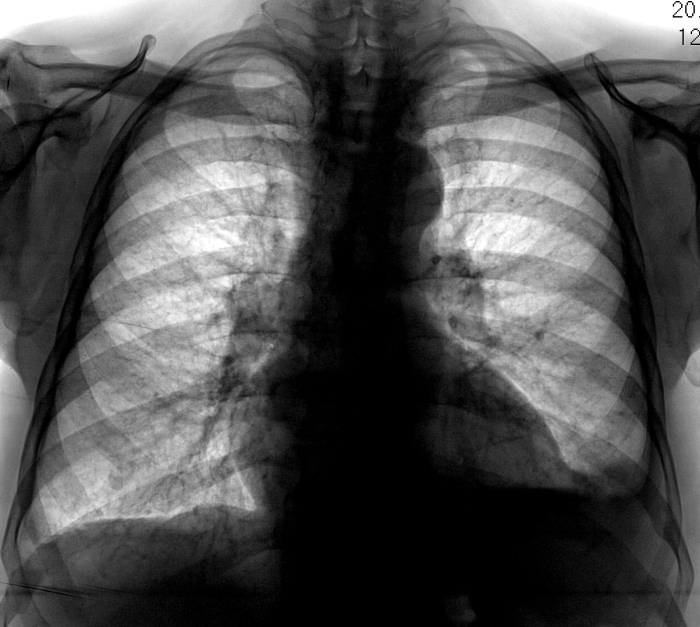

Пол пациента: Мужской пол Тип патологии: Другое Область исследования: Грудная клетка и верхние дыхательные пути Методы исследования: Rg Направлен на рентгенографию ОГК с подозрением на левостороннюю пневмонию. 2. https://radiomed.ru/sites/default/files/styles/case_slider_image/public/user/12/12.201411050032.jpg?itok=dJ8_3Oxo https://radiomed.ru/sites/default/files/styles/case_slider_image/public/user/12/13.201411050033.jpg?itok=fmadLMvN ID:56752 Пт, 07/11/2014 - 15:23 #1 NIL Не на сайте Был на сайте: 6 часов 38 минут назад Зарегистрирован: 25.11.2013 - 20:50 Публикации: 18206 Гидроторакс слева, на фоне которого что-то шаровидное. Латерографию бы (для начала). "Слушай всех, прислушивайся к немногим, решай сам".© Пт, 07/11/2014 - 16:26 #2 Сергей Кузьминов Не на сайте Был на сайте: 1 год 2 недели назад Зарегистрирован: 06.10.2012 - 15:51 Публикации: 11813 Нет.Для начала-контроль после пункции. Пт, 07/11/2014 - 21:20 #3 И.Бондаренко Не на сайте Был на сайте: 2 дня 5 часов назад Зарегистрирован: 13.09.2011 - 22:55 Публикации: 9206 +1 Пнд, 10/11/2014 - 12:36 #4 Катенёв Валенти... Не на сайте Был на сайте: 7 лет 2 недели назад Зарегистрирован: 22.03.2008 - 22:15 Публикации: 54876 "Шаровидное" - по боковой? Пнд, 10/11/2014 - 12:54 #5 NIL Не на сайте Был на сайте: 6 часов 38 минут назад Зарегистрирован: 25.11.2013 - 20:50 Публикации: 18206 И на прямой тоже естьПриложения: "Слушай всех, прислушивайся к немногим, решай сам".© Пнд, 10/11/2014 - 12:56 #6 Катенёв Валенти... Не на сайте Был на сайте: 7 лет 2 недели назад Зарегистрирован: 22.03.2008 - 22:15 Публикации: 54876 Если по прямой, так с другой стороны точно такой...

Гидроторакс слева, на фоне которого что-то шаровидное. Латерографию бы (для начала).

И на прямой тоже есть

Если по прямой, так с другой стороны точно такой...